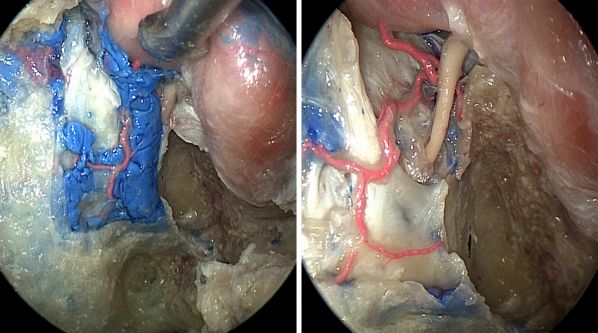

图13:内镜下经鼻经岩斜入路切除左侧岩斜区软骨肉瘤(最上排图)。第二排图中标明手术入路相关解剖标志。第三排图所示为角度内镜下用成角环形刮匙切除隐藏在颈内动脉岩骨段内侧的肿瘤。最下图所示为术区最终情况。图中蓝色箭头所指为轮廓化的颈内动脉进入海绵窦的位置。这种手术经颅入路显露非常艰难。